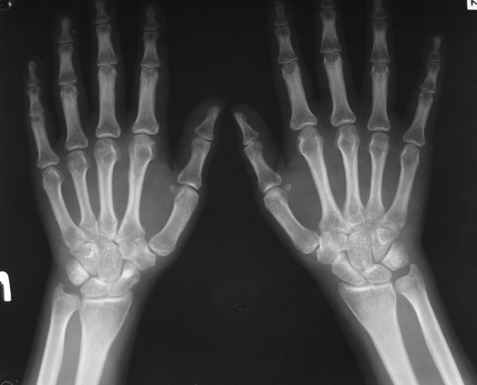

Уважаемые коллеги! Вопрос по уточнению диагноза. Методы дополнительной диагностики? Вашемнение по данному случаю?Спасибо!

Женщина, 30 лет.

Жалобы на сильные боли в суставах и мышцах (без четкой локализации), припухлость суставов, повышение температуры 38-39 гр.

Считает себя больной с 1994 г., когда появились боли в легких. В 1996 г. - боли в спине без четкой локализации. 2002 г. - роды, через 10 мес. сильные мышечные боли. 2004 г. - плеврит и увеит (сейчас - миопия, -1,-1,5, астигматизм). Периодические увеличения лимфатических узлов (чаще шейных), симптомы васкулита.

Диагноз: Ревматоидный артрит неизвестной этиологии (реактивный урогенитальный артрит или полиартрит?)